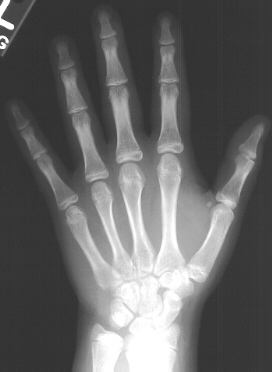

The patient demonstrated a large pigmented lesion with irregular border located in the right upper back. There was a two centimeter leg length discrepancy by the block test. X-rays showed an expansile radiolucent area with a ground glass density involving the right proximal femur . There was a healing transverse subtrochanteric fracture involving the lateral cortex . There was also an expansile lesion noted in the midshaft of the right fibula . A scanogram revealed a 1. 8 cm leg length discrepancy with right leg shorter than left . Bone age was 14 years old ( 4 years advanced) .

RADIOGRAPHIC:

Fibrous dysplasia is an intramedullary diaphyseal /metaphyseal lesion that blends with a thinned, slightly bulged cortex. The cortex of the affected bone may be thinned by endosteal erosion which creates a scalloped pattern. In long bones, the lesions are usually metaphyseal in location, extending into the rnid-diaphysis. The lesion has a homogenesis density @g it a so-called "ground glass" appearance. An angular deformity in the bone is often present at the level of the lesion. Periosteal reaction is absent except when a pathologic fracture is present. Bone scans show increased uptake-can assess the extent and multiplicity of involvement. CT scan is helpful in differentiating eosinophilic granuloma, osteomyelitis, and unicameral bone cyst. These show lower Hounsfield units (O to 40), compared to fibrous dysplasia (70 to 130). Few studies other than plain X-rays are required in a typical case of polyostotic disease.